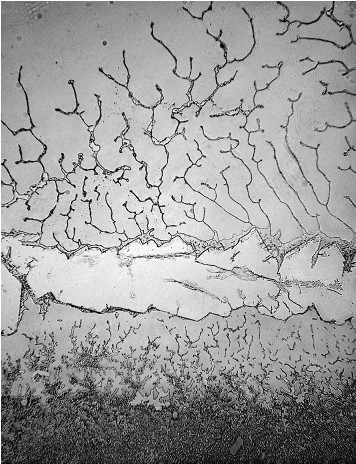

Dacă, pe aceste tipuri diferite de lacrimi, dar și pe altele, punem microscopul, la propriu, vom putea observa lucruri total surprinzătoare.

Cercetătorii Institutului de Oftalmologie din Madrid au analizat la microscop textura diferitelor lacrimi, iar rezultatul a fost unul neașteptat.

Compoziția lor poate părea asemănătoare sau chiar identică, uneori. Singura diferență constatată de noi, adesea, este gustul lacrimilor care pote fi, uneori, mai sărat, însă o imagine detaliată ne demonstrează că, în realitate, nu este deloc așa.

Fiecare categorie este diferită de cealaltă, iar compoziția lor diferă în funcție de sentimentele noastre.

Diferența o fac sentimentele exprimate prin intermediul lacrimilor, sunt de părere cercetătorii.

În funcție de situația în care se află sistemul neuroendocrin, în lacrimi se secretă diferite tipuri de hormoni și neurotransmițători, de a căror cantitate și tipologie depinde compoziția moleculară a lacrimilor înainte ca acestea să apară în exterior.